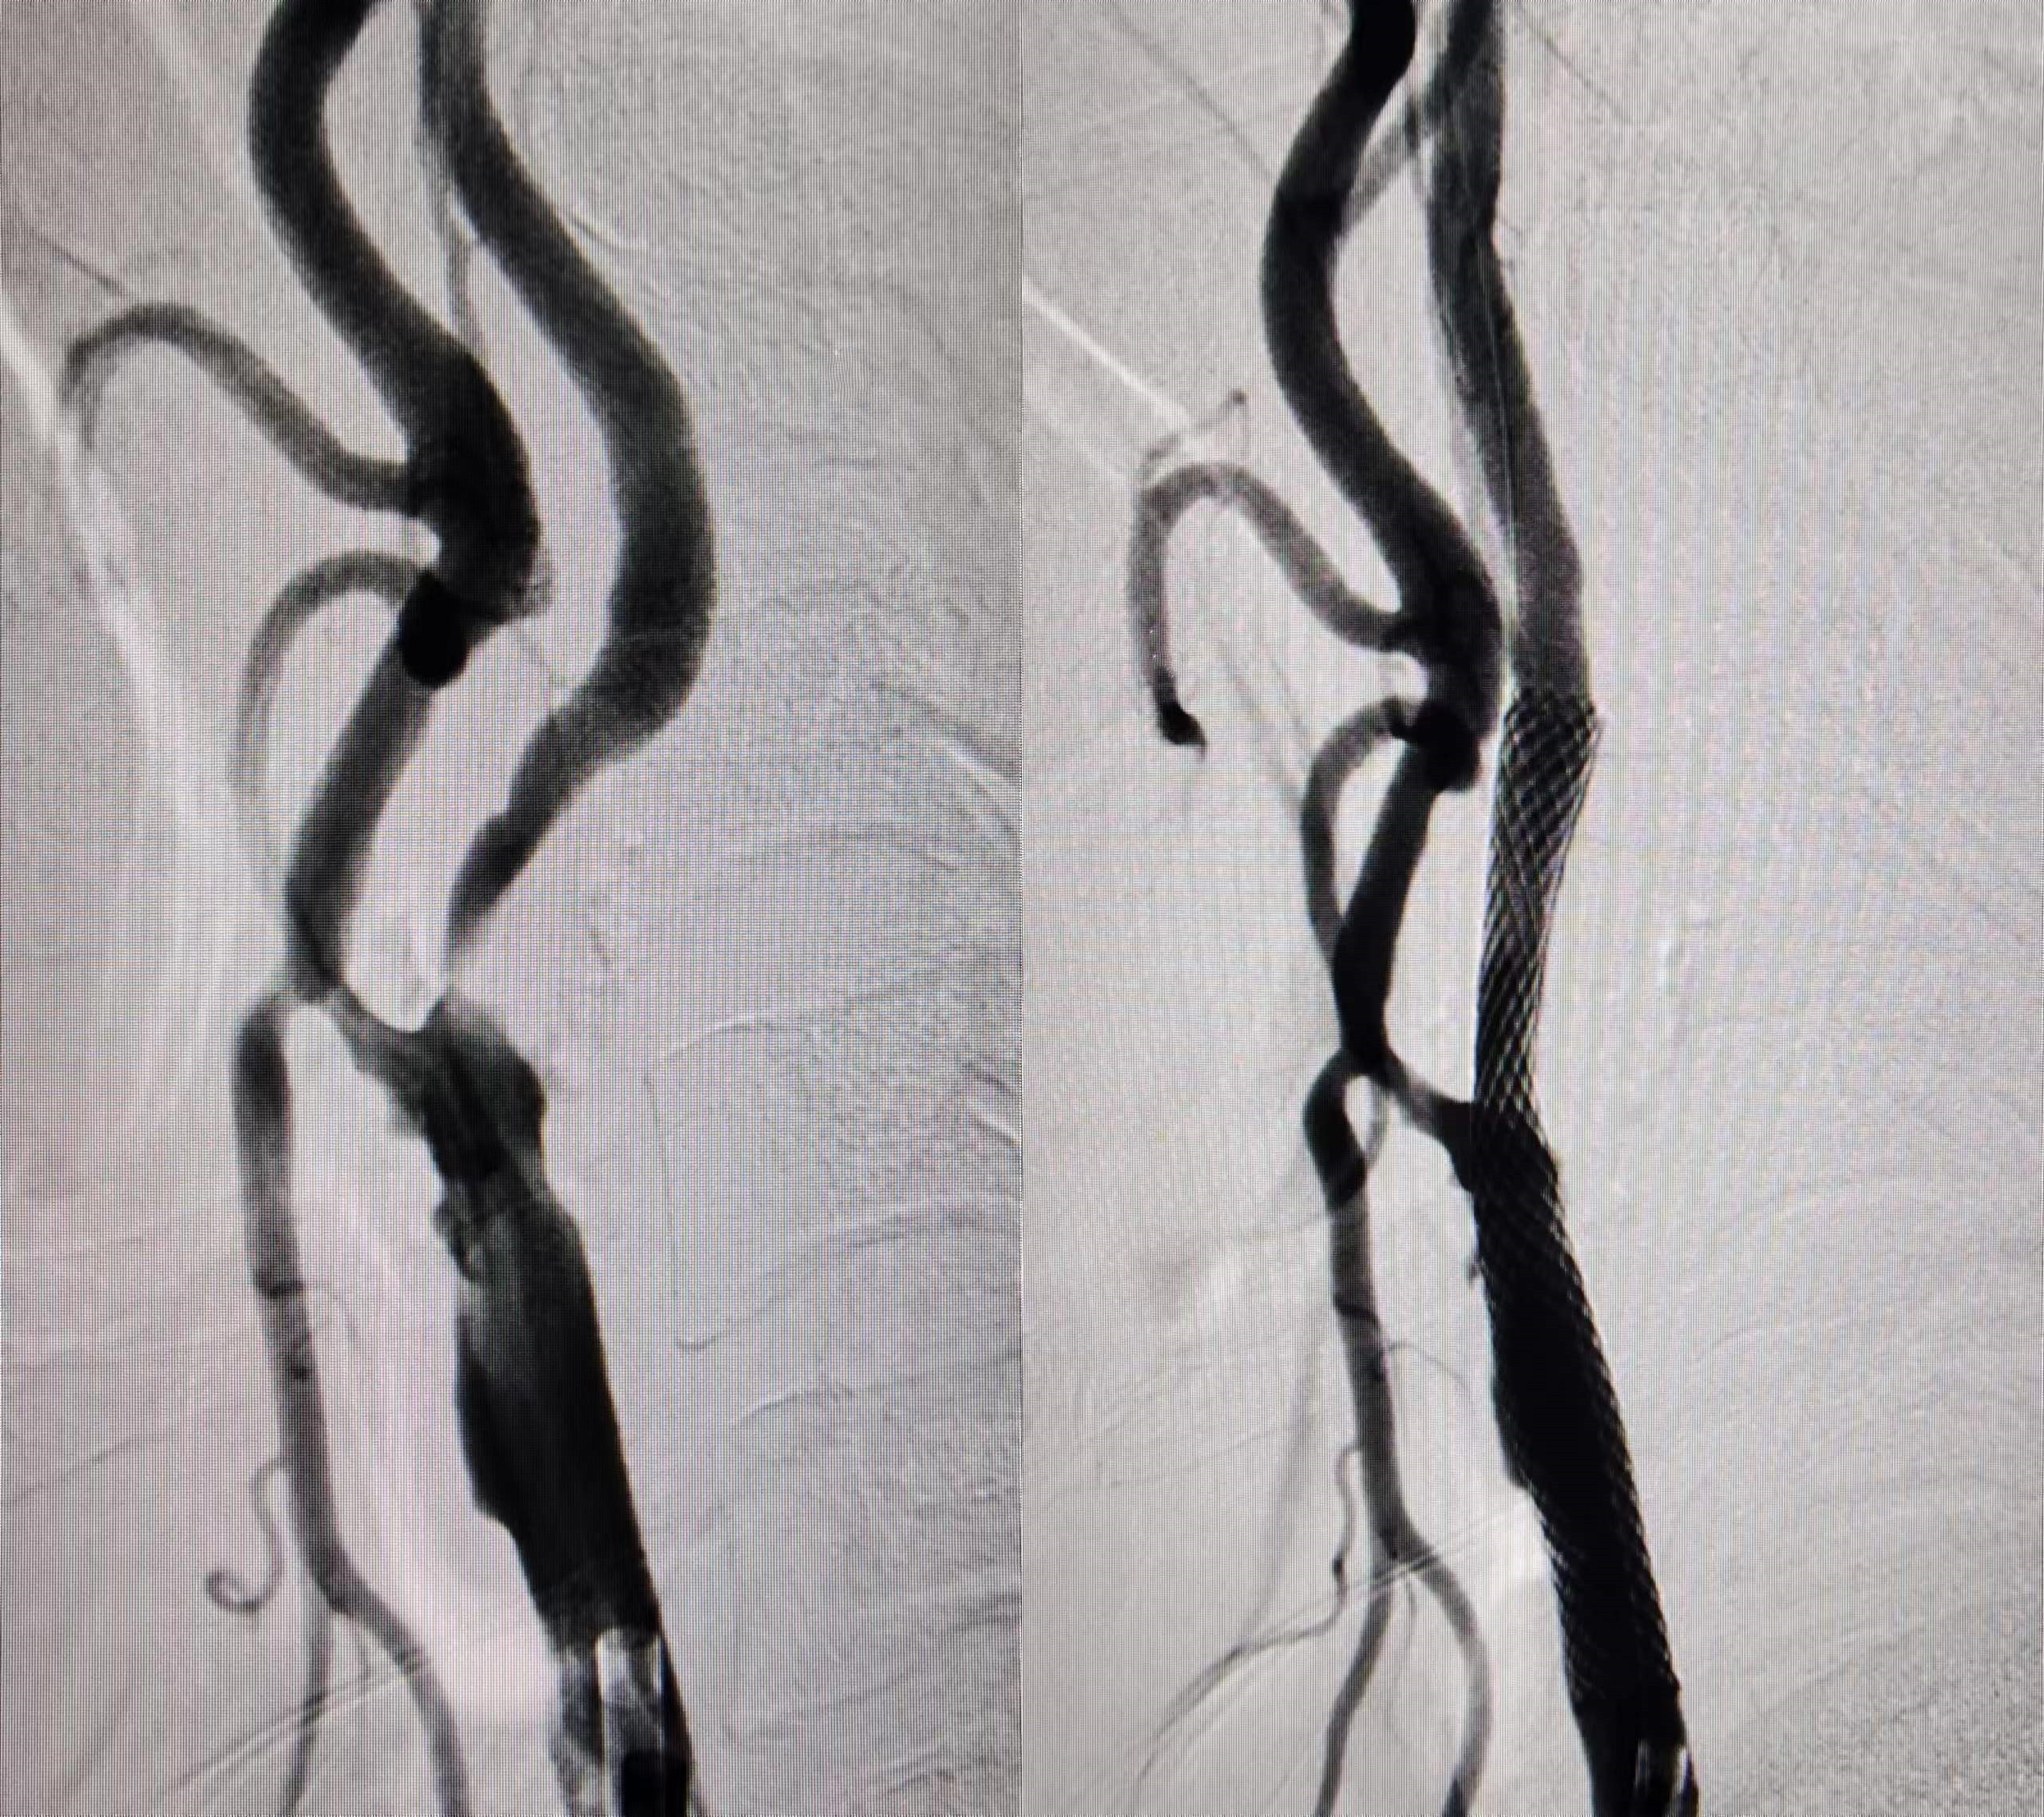

在进行了充分的术前评估并制定了周密的手术方案后,神经内科一病区副主任、副主任医师顾汉沛带领卒中中心团队为张大爷行脑保护伞下颈动脉支架置入术。术后造影显示颈内动脉扩张良好,远端显影良好。

▲图为患者术前、术后血流图